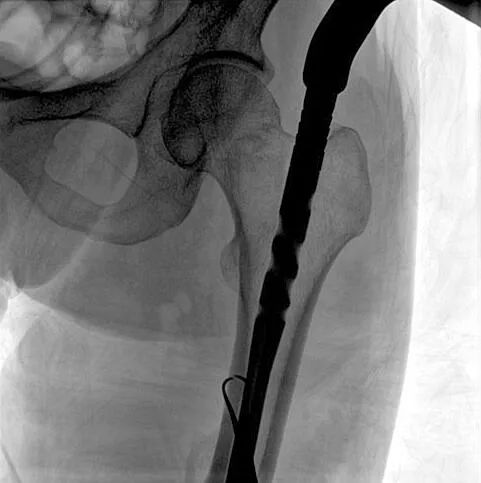

C形臂輔助手術(shù)過程

術(shù)中使用普愛醫(yī)療大平板一體式C形臂進行透視,判斷骨折情況及克氏針、髓內(nèi)釘?shù)冉饘僦踩胛锏奈恢茫M行調(diào)整。C形臂準確的術(shù)中定位,大大縮短了手術(shù)的時間,減輕了患者的痛苦,輔助手術(shù)順利完成。

術(shù)中定位準確、出血量少,術(shù)后影像顯示股骨移位糾正,恢復(fù)良好力線,手術(shù)效果良好。